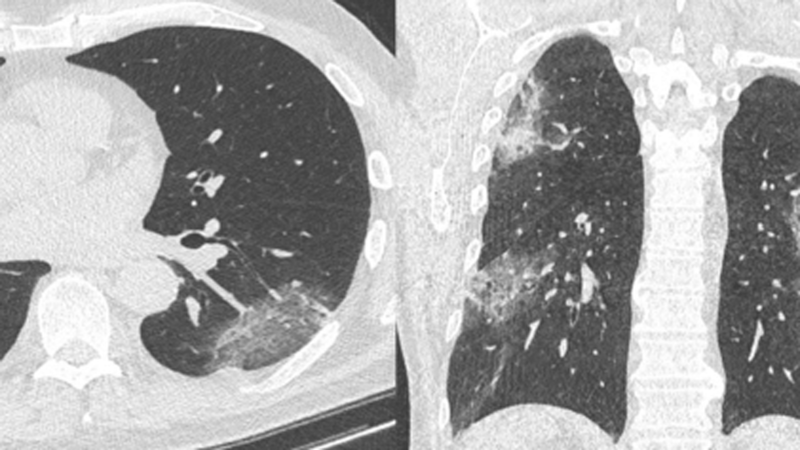

CT-Befunde können Veränderungen beschreiben, die nicht spezifisch sind für die Diagnose von COVID-19, sondern auch bei anderen Viruspneumonien vorkommen. Die CT kann deshalb im interdisziplinären Zusammenhang zur Beurteilung der individuellen Prognose von Patienten beitragen, sollte aber weder als Screening-Test noch zur Triage bei Patienten mit nicht schweren oder keinen Symptomen durchgeführt werden. Die wichtigste Aufgabe der CT im Rahmen der COVID-19-Pandemie ist vielmehr die Diagnose von Pneumonie-assoziierten Komplikationen sowie die Bewertung des initialen Krankheitsausmaßes und die Verlaufsbeurteilung. Sie unterstützt damit die klinische Einschätzung von besonders schweren Erkrankungsfällen.

Eine negative CT-Diagnostik schließt COVID-19 nicht aus. Auf der anderen Seite kann eine CT bei negativer initialer PCR die Verdachtsdiagnose stellen, welche dann durch serielle PCR-Tests bestätigt werden muss. Prof. Dr. Gerald Antoch, DRG-Präsident: „Bei einem klinisch symptomatischen Patienten, initial negativer PCR und klinischer Konsequenz kann die CT die Diagnose COVID-19 stellen. Wichtig ist nachfolgend die Bestätigung des CT-Befundes durch sequenzielle RT-PCRs.“ Der primäre Test für die Diagnose von SARS-CoV-2 ist und bleibt daher die RT-PCR.